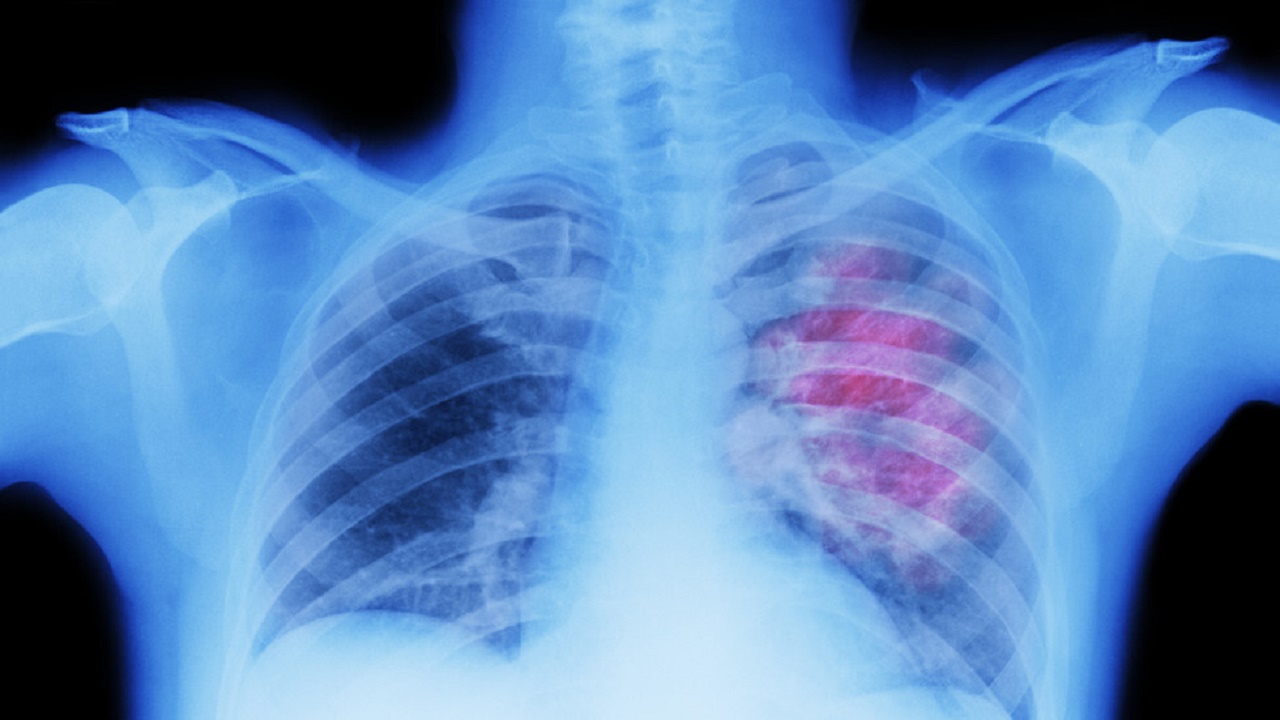

الشعب الهوائية

الصحة توضح حقيقة علاج الشعب الهوائية باستنشاق الزعتر

وصفة سريعة لتوسيع الشعب الهوائية